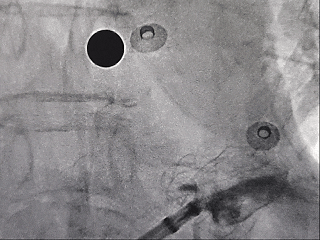

肝位输送LAFDQ-29封堵器

封堵器展开后造影

肝位

头位

牵拉试验后造影

牵拉稳定,且造影无残余分流。